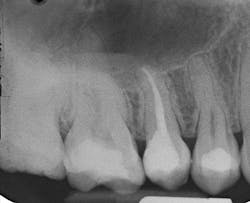

Ease of placement can help practitioners be more efficient during direct resin placement, but a feature which should not be overlooked is radiopacity. Some early flowable composite resin products had radiopacities less than enamel on follow-up radiographic exams, and when placed as liners in deep cavity preparations, appeared as a void or recurrent decay on radiographs. Newer generations of flowables have a radiopacity greater than enamel and dentin, which allows the clinician to visualize the restoration and differentiate it from surrounding structures.

A 20-year-old female patient presented for a core buildup on tooth No. 4 following unremarkable root canal therapy. The tooth was isolated with a Palodent Plus Sectional Matrix System, and Prime&Bond Elect Universal Adhesive (Dentsply Sirona) was applied per manufacturer’s directions (figure 2). An initial 1 mm layer of SureFil SDR flow+ universal shade was placed over the gutta percha and light cured.